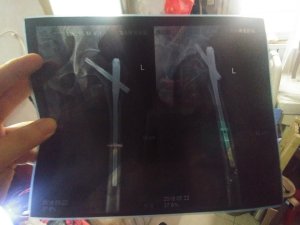

2018年5月初,当我骑着电动三轮车载运家具到达定陶青年路南段时,忽觉头痛难忍,耳畔似乎响起啸叫之类的声音,紧接着,我彻底失去控制,电动车把剧烈向右打转,电动车猛然撞至护栏上,我被巨大的反弹力弹离了座位,以左侧身体摔落方式,遽然摔在公路面,头、左臂、以及左腿(主要是左髋关节处),疼痛难忍。我挣扎着爬起来时,左腿已然是半麻痹状态,有些动作是左腿没法做的,一旦不慎做了,顿有裂骨之巨痛。恰在这时,父母退休前所工作的定陶实验中学的同事徐伯伯经过此地,认出了是我,帮我打了急救电话,并和救护车上的护理人员一起将我抬到救护车上。经医院检测,髋骨等处接近粉碎骨折,骨头上出现了多数裂缝。两周后,我在家人陪同下,在菏泽博爱医院做了手术,在左髋、股骨处进行了内固定,亦即,打了几处钢板。

图j 2018年出院前后拍的关于骨折部位的片子

图k 2018年出院前后拍的关于骨折部位的片子